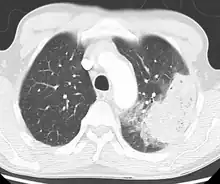

Cavitating pneumonia due to MRSA as seen on a CT scan

Bacteria are the most common cause of community-acquired pneumonia (CAP), with Streptococcus pneumoniae isolated in nearly 50% of cases.[34][35] Other commonly isolated bacteria include Haemophilus influenzae in 20%, Chlamydophila pneumoniae in 13%, and Mycoplasma pneumoniae in 3% of cases;[34] Staphylococcus aureus; Moraxella catarrhalis; and Legionella pneumophila.[18] A number of drug-resistant versions of the above infections are becoming more common, including drug-resistant Streptococcus pneumoniae (DRSP) and methicillin-resistant Staphylococcus aureus (MRSA).[21]